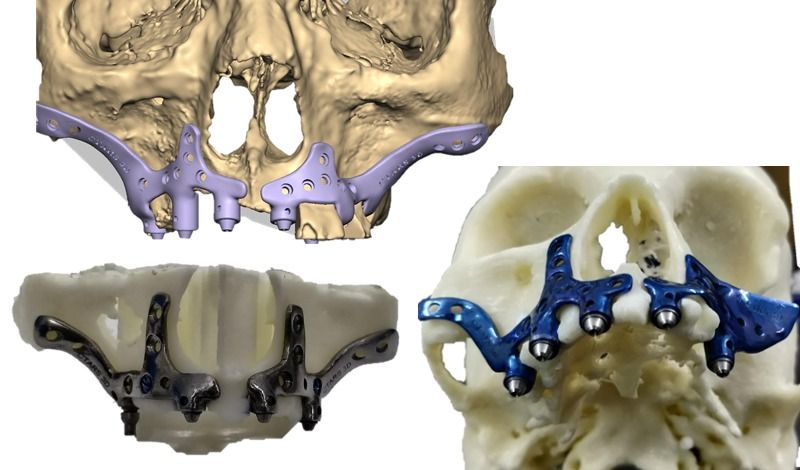

Elevate your dental care journey with our membership program, specifically designed for patients seeking teeth implants. As a member, you’ll benefit from reduced pricing on implant procedures, priority scheduling for consultations and treatments, and continuous follow-up care to ensure the best outcomes. Join today to access top-tier dental implant services and enhance your smile with confidence.